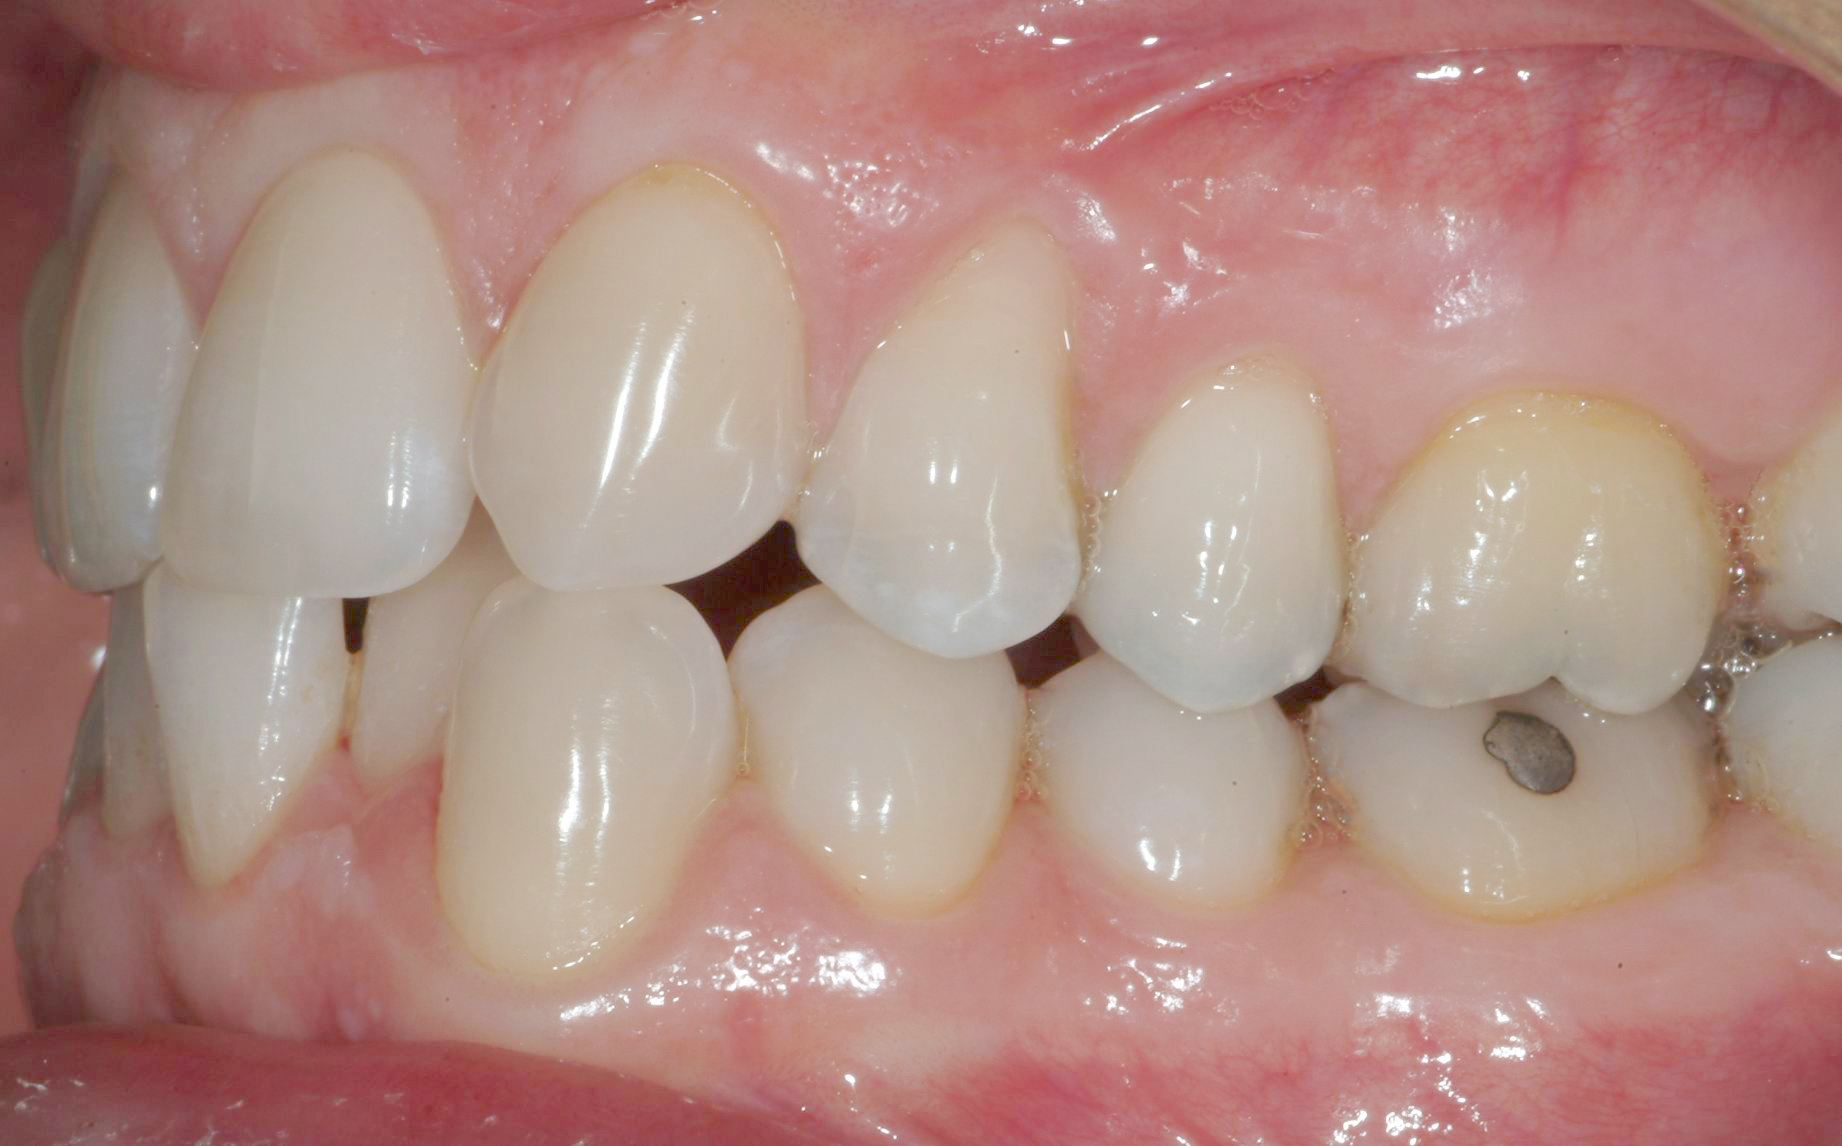

Per formulare corretta diagnosi e piano di cura, lo studio del caso ha previsto la raccolta di documentazione completa standard, ovvero fotografie del viso e intraorali (Figure 1a-e), radiografia panoramica e teleradiografia del cranio in proiezione laterale (Figure 2a-b) per la relativa analisi cefalometrica e modelli di studio.

La valutazione clinica e gli esami effettuati confermano la presenza di agenesia degli incisivi laterali superiori (1.2 e 2.2) e del secondo premolare inferiore destro (4.5).

L’analisi ortodontica e la valutazione parodontale, con particolare riferimento alla posizione della radice del canino superiore destro (1.3), distoinclinata e trasposta alla radice del primo premolare (1.4) come evidente dalla radiografia panoramica e dalle immagini intraorali, ci hanno guidati nella programmazione di un trattamento estrattivo asimmetrico a entrambe le arcate.